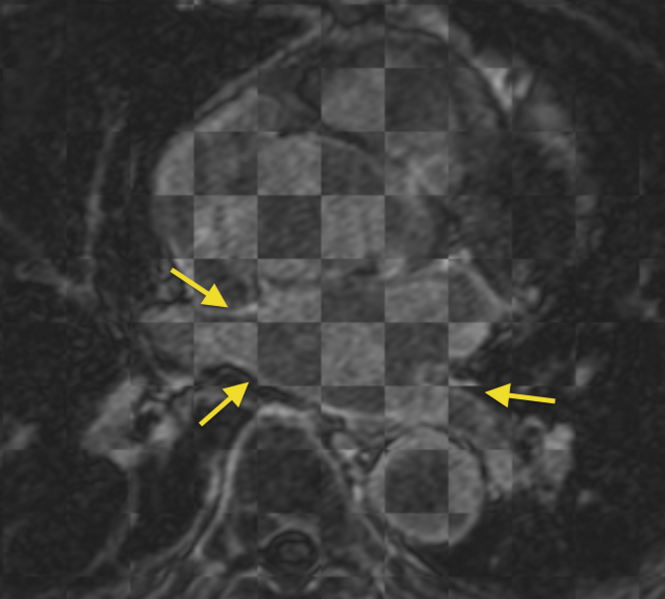

An example of the misregistration that is seen when trying to register the pulmonary veins of pre- and post-ablation LGE-MRI scans from the same patient (scans acquired roughly 3 months apart). Registration was attempted through automatically generated correspondence points within the whole image volume.

current17:42, 9 January 2012Thumbnail for version as of 17:42, 9 January 2012669 × 603 (268 KB)Ggardner (talk | contribs)An example of the misregistration that is seen when trying to register the pulmonary veins of pre- and post-ablation LGE-MRI scans from the same patient (scans acquired roughly 3 months apart).